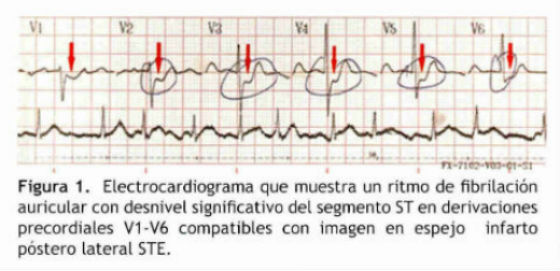

Electrocardiograma: Fibrilación auricular, respuesta ventricular alta. Segmento ST deprimido 1-2 mm en derivación V1, V2, V3, V4, V5 y V6 (Figura 1).

Nuestra paciente presentó IMSTE dentro del contexto de FA paroxística, los hallazgos electrocardiográficos inicialmente fueron interpretados como un IMSTNE por la depresión del segmento ST en múltiples derivaciones anteriores.

Los hallazgos muestran la presencia de coágulo obstructivo total de la arteria coronaria derecha (CD) en su ramo ventricular posterior, de allí la presencia del segmento ST deprimido como espejo de la elevación ST en la cara posterior del ventrículo izquierdo.